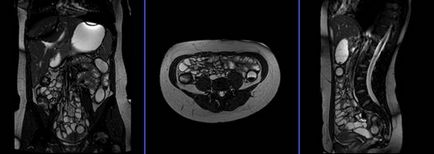

A primer szekvenciája a tervezési kell végezni képek 3 síkban TrueFISP. Ez a rövid, gyors egyetlen lövés 25 másodperc expozíciós, tökéletesen tükrözi a hasi szerveket.

Tervezés koszorúér szeletek axiális síkban; szöghelyzete a blokk keresztirányban, hogy a has, ábrán látható módon. Ellenőrizze a helyét a blokk a 2 másik síkon. Ezek között a szakaszok, hogy teljesen befedje a teljes hasüreget a hasfal elülső és a hátsó hasfal. A látómező (FOV) elegendőnek kell lennie, hogy fedezze a has és a medence a gyomor, hogy a szint a fancsonti. Annak megakadályozása érdekében műtermékek GDV kell használni fázist túlmintavételezésre (túlmintavételezés). Fontos, hogy a beteget a levegőt-hold alatt képrögzítő csomagokat. (A mi osztály, azt utasítják a pácienseket be és ki kétszer, mielőtt „be és tartsa vissza a lélegzetét” elején a scan).